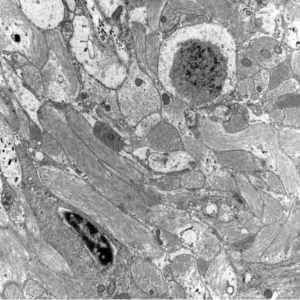

- polyglucosan bodies include a number of ultrastructurally similar inclusions

- can be nonspecific:

- in axons of the CNS and PNS related to aging

- corpora amylacea in astrocytic processes

- staining properties of polyglucosan bodies:

- stains with PAS, BEST's carmine for glycogen, iodine, Alcian blue

- not stained by Congo red

- can show metachromasia with toluidine blue

- Lafora bodies and corpora amylacea are spheroid

- Bielschowsky bodies are elongated, located in neuronal perikarya and dendrites, isolated to the basal ganglia, sometimes near status marmoratus (post perinatal hypoxic damage)

- infantile type IV glycogenosis

bodies in astrocytes in subpial, subependymal, and perivascular regions, both in grey and white matter

- Lafora disease

- Lafora bodies in grey matter in both neuronal perikarya and neuronal processes, mostly in the subcortical grey matter including brainstem and cerebellar nuclei

- loss of nerve cells corresponding to density of Lafora bodies

- can appear in ganglionic and bipolar cells of retina

- outside of CNS, in epithelial cells of eccrine sweat gland ducts, skeletal muscle fibers, and cells of the PNS

- Adult polyglucosan body disease

neuronal processes and astrocytes in both grey and white matter, also spinal cord and PNS

Immunohistochemistry and Ultrastructural Findings

- polyglucosan bodies - in axons

- Lafora bodies - in neuronal perikarya and dendrites

Lafora bodies (temporal lobectomy)